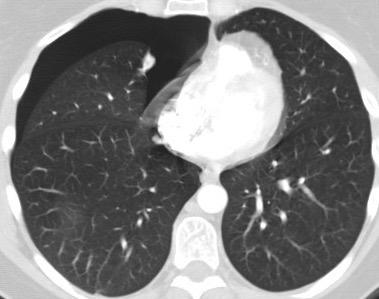

Derrame pleural 43-48% de pacientes con embolismo.

< 1/3 de hemitórax: 90%.(puede haber en lado opuesto).

Siempre exudados.

75% de los pacientes con TEP y derrame pleural tienen dolor pleurítico.

La disnea desproporcionada

Joroba de Hampton

Hallazgo muchas veces incidental.